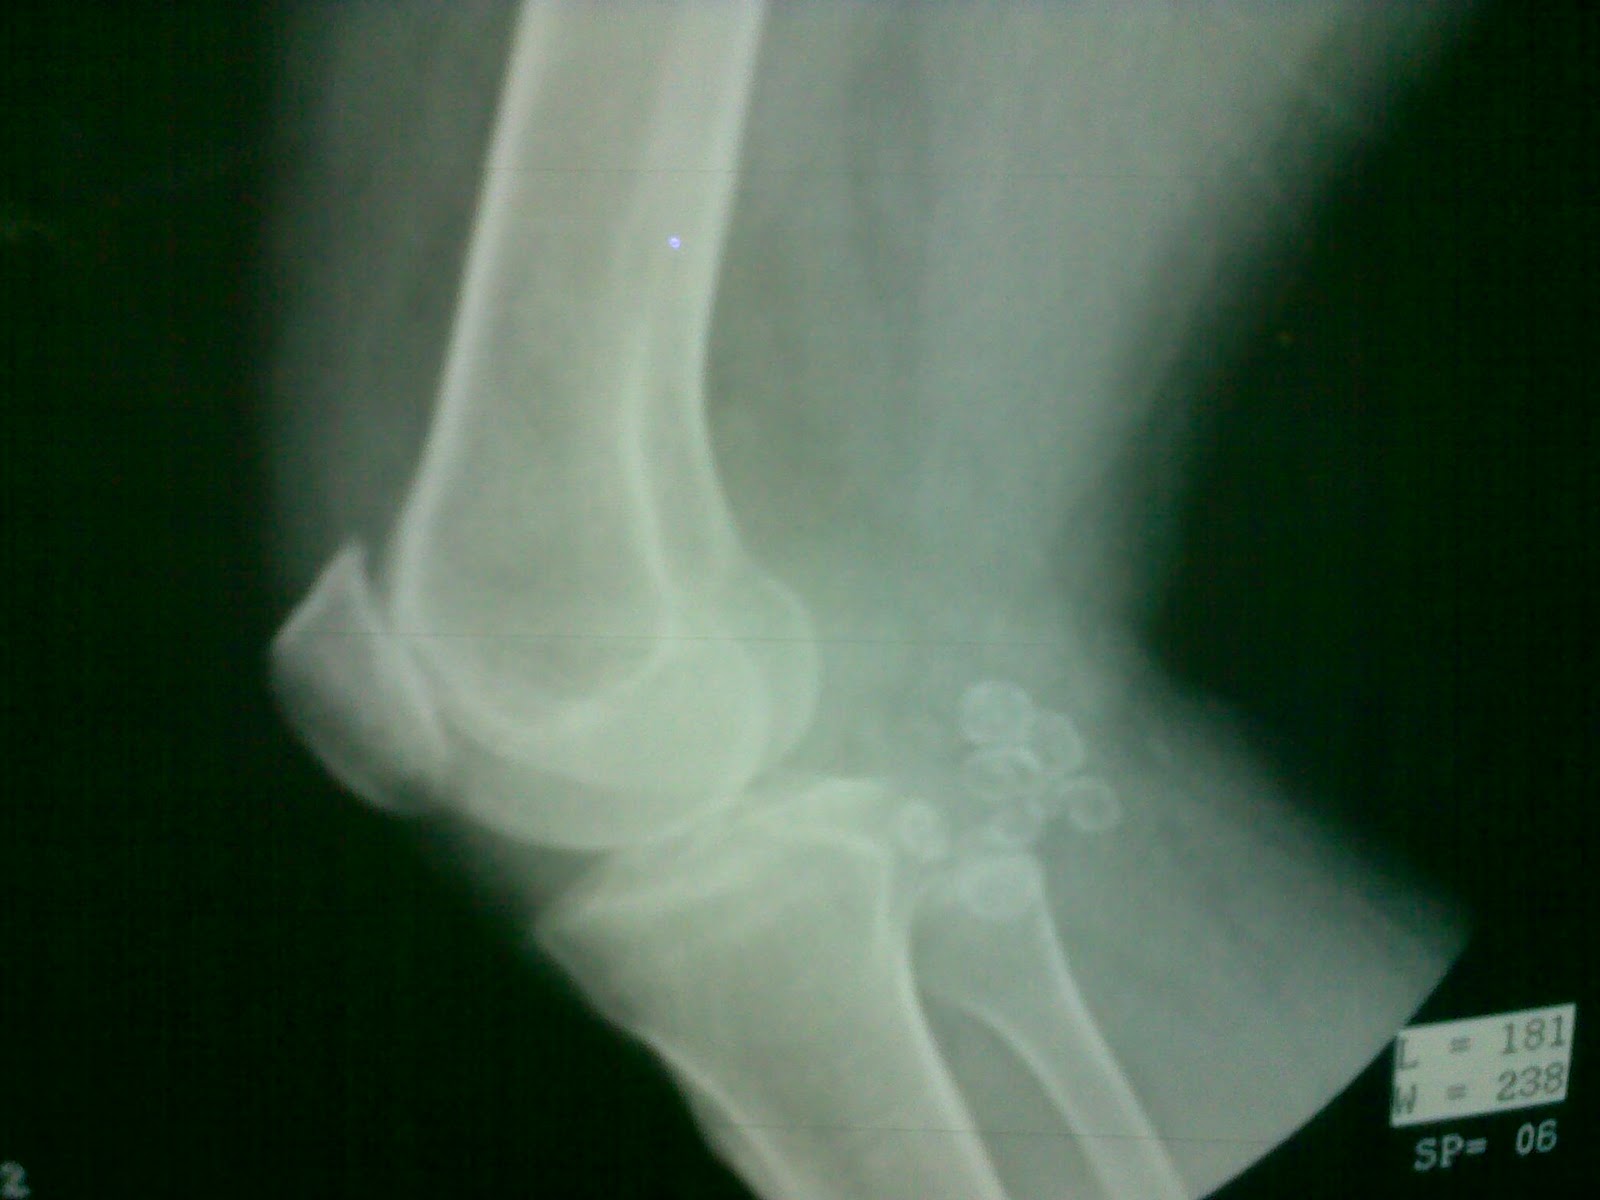

| Photo Credit: AKha CC-BY-SA-3.0 2011 |